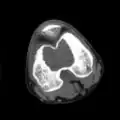

| Chondoblastoma of thigh bone near knee (CT scan, non-contrast) | |

1. a. X-ray of chondroblastoma of thigh bone near knee -

1. b. CT scan shows chondroblastoma of thigh bone near knee more clearly -

1. c. CT scan of chondroblastoma of thigh bone near knee (cross-section view) -